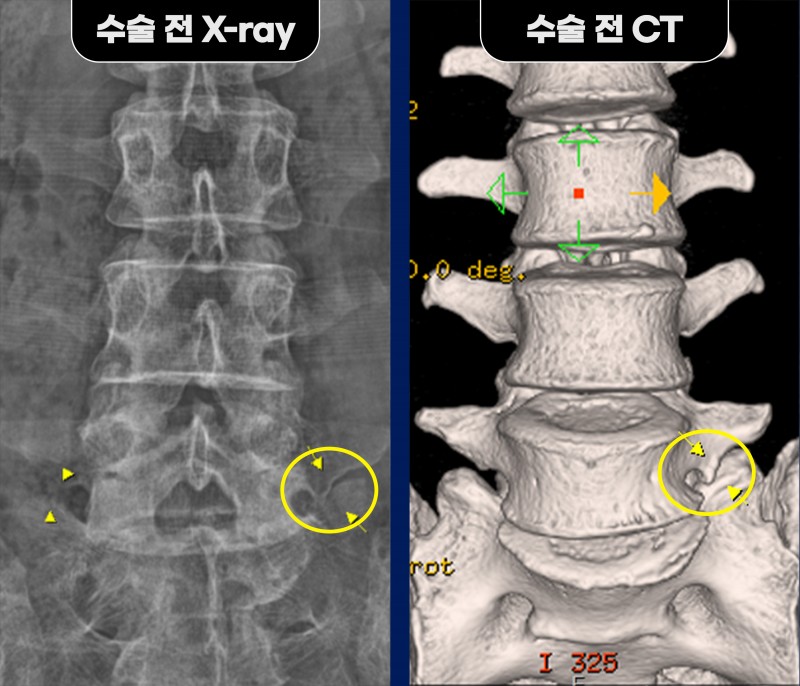

정밀 검사 결과, 단순 협착증이 아닌 요추 5번과 천추 1번이 부분적으로 붙어 가관절을 형성한

‘베르톨로티 증후군(Bertolotti syndrome)’으로 확인되었습니다.

좌측 요추 5번/천추 1번 추간공 확장술과 함께 횡돌기와 천추 날개뼈 사이의 가관절을 제거하고,